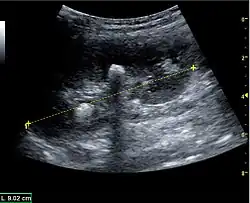

Masses are seen as a distortion of the normal renal architecture. Most renal masses are simple cortical renal cysts with a round appearance and a smooth thin capsule encompassing anechoic fluid. The incidence increases with age, as at least 50% of people above the age of 50 have a simple cyst in one of the kidneys. Cysts cause posterior enhancement as a consequence of reduced attenuation of the ultrasound within the cyst fluid (Figure 5). The simple cyst is a benign lesion, which does not require further evaluation.[1]

Figure 5. Simple renal cyst with posterior enhancement in an adult kidney. Measurement of kidney length on the US image is illustrated by '+' and a dashed line.[1] -